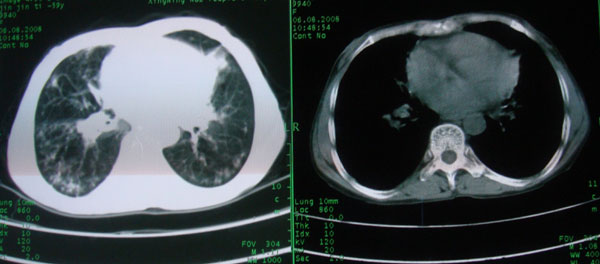

多考虑支气管扩张并感染,双下肺继发性肺结核不除外

周围型肺癌征象不明显,应不予首先考虑

考虑支气管肺泡癌可能性大

慢性支气管炎伴支气管扩张、感染,间质纤维化。

慢性支气管炎伴全小叶型肺气肿、支气管扩张、感染、间质纤维化